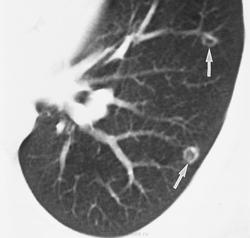

Онкология. ОГК. Полостные (кавитирующие) метастазы. "Атипичные" метастазы. +

"Полостные" метастазы

Множественные метастазы.